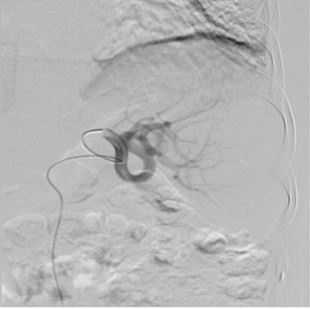

Due to the fact that intraoperative blood loss is a common occurrence in splenectomy, the authors set out to compare the perioperative and clinical outcomes of splenic artery embolisation (SAE) prior to splenectomy versus splenectomy alone. On a total of 100 patients, the authors concluded that perioperative SAE in splenectomy patients significantly reduced the need for blood transfusion when compared to patients who underwent splenectomy alone.

Article: Splenectomy for hypersplenism with or without preoperative splenic artery embolisation